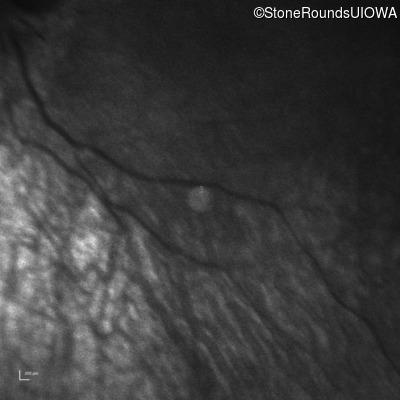

Infrared Fundus Photograph - Right -

Light Perception

Exemplar